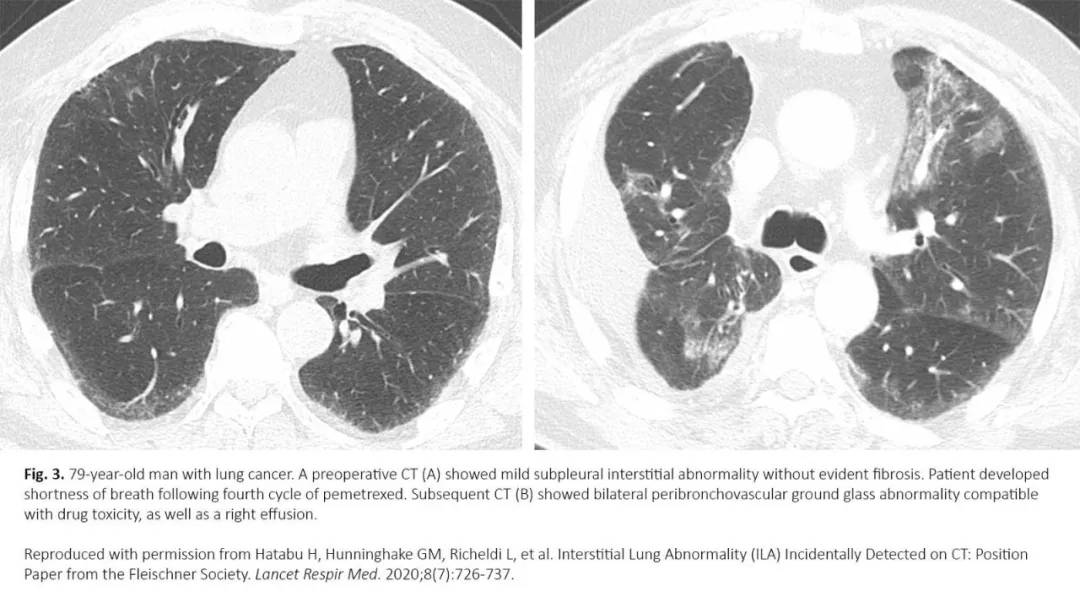

图3. 一位79岁肺癌患者化疗后肺间质异常

最近的研究表明,治疗前存在ILA与癌症相关死亡率之间存在关联,包括接受手术切除的早期肺癌患者,以及晚期、IV期疾病和系统损伤患者。8-12观察到有ILA患者的癌症死亡率增加,其实际原因尚不清楚,但研究表明,与ILA和癌症治疗相关的肺损伤可能是重要原因。事实上,肺部放疗、化疗、TKI、免疫检查点抑制剂、抗体-药物偶联物等系统治疗使得ILA患者发生肺炎的风险增加(图3)。